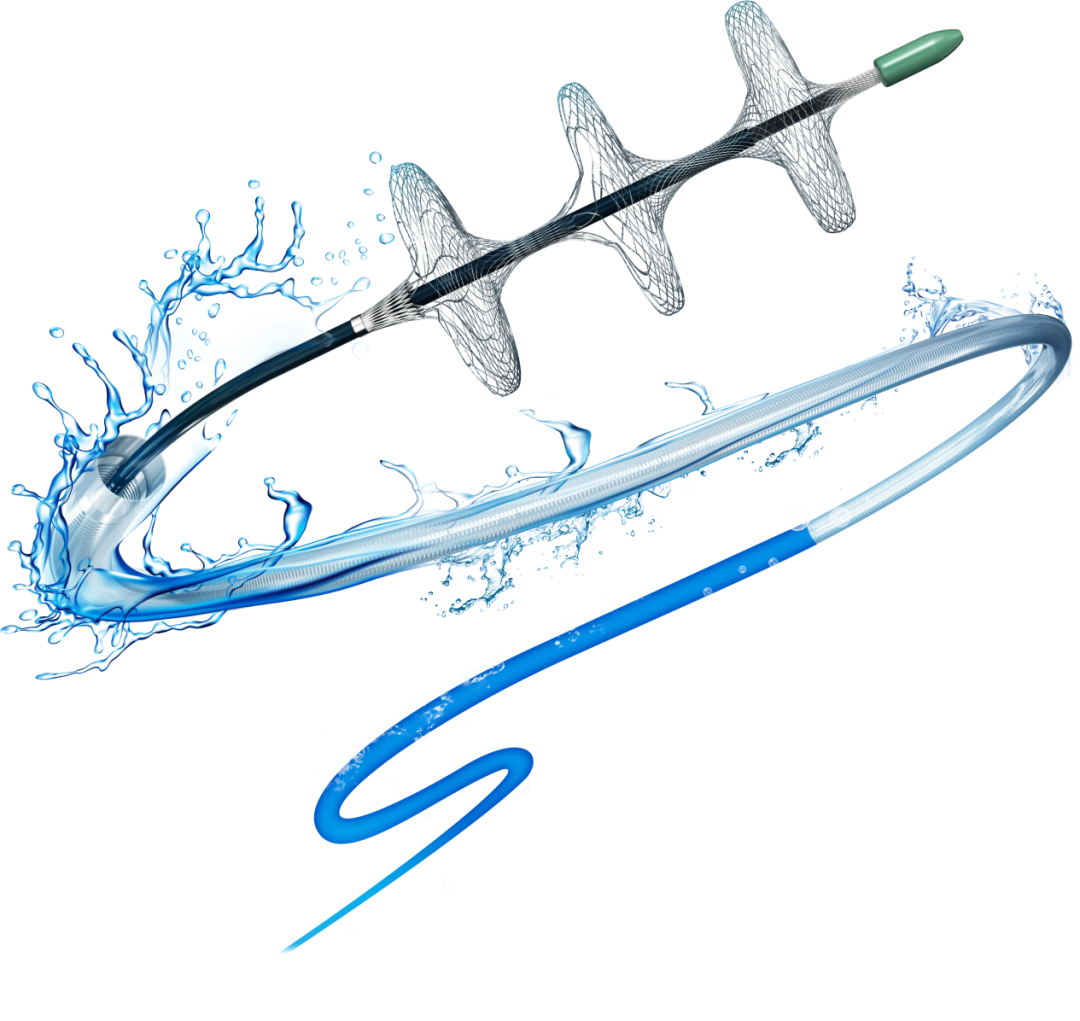

Tendvia™肺动脉取栓⽀架系统

2024 年 5月Tendvia™肺动脉取栓⽀架系统( 国械注准20243031010)获得国家药品监督管理局( NMPA)批准上市!Tendvia™肺动脉取栓支架系统作为全国首款急性肺动脉栓塞专用介入器械 ,填补了我国肺动脉取栓支架治疗肺栓塞领域的空白 。

该产品可适用于有下述情况之⼀的急性中高危肺栓塞或伴临床恶化的中危肺栓塞的经导管血栓清除治疗:

有肺动脉主干或主要分支血栓 ,并存在高出血风险或溶栓禁忌的患者;

有肺动脉主干或主要分支血栓 ,并经溶栓或积极的内科治疗无效的患者。